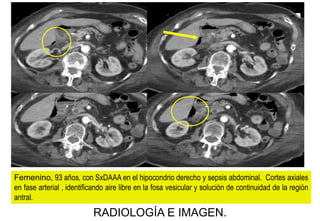

Femenino, 93 años, con SxDAAA en el hipocondrio derecho y sepsis abdominal. Cortes axiales

en fase arterial , identificando aire libre en la fosa vesicular y solución de continuidad de la región

antral.

IMPRESIÓN TOMOGRÁFICA:

ULCERA ANTRAL PERFORADA

QUIRÚRGICO:

Femenino, 93 años, con SxDAAA en el hipocondrio derecho y sepsis abdominal.